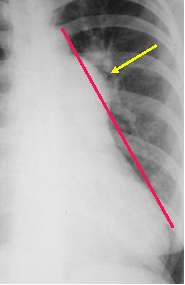

Main

pulmonary

artery

projects

beyond

tangent

Increased

pressure

Increased flow